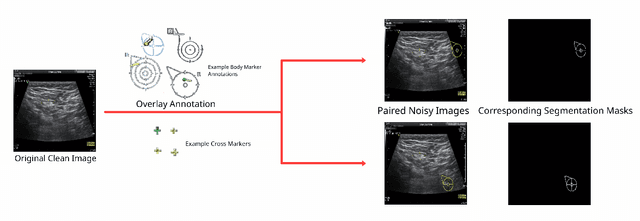

Abstract:Accurately annotated ultrasonic images are vital components of a high-quality medical report. Hospitals often have strict guidelines on the types of annotations that should appear on imaging results. However, manually inspecting these images can be a cumbersome task. While a neural network could potentially automate the process, training such a model typically requires a dataset of paired input and target images, which in turn involves significant human labour. This study introduces an automated approach for detecting annotations in images. This is achieved by treating the annotations as noise, creating a self-supervised pretext task and using a model trained under the Noise2Noise scheme to restore the image to a clean state. We tested a variety of model structures on the denoising task against different types of annotation, including body marker annotation, radial line annotation, etc. Our results demonstrate that most models trained under the Noise2Noise scheme outperformed their counterparts trained with noisy-clean data pairs. The costumed U-Net yielded the most optimal outcome on the body marker annotation dataset, with high scores on segmentation precision and reconstruction similarity. We released our code at https://github.com/GrandArth/UltrasonicImage-N2N-Approach.